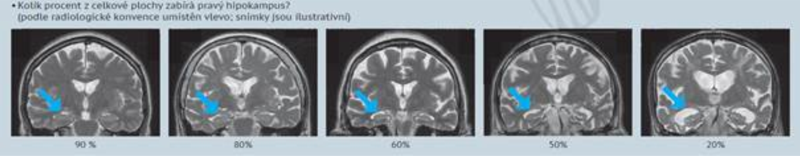

Při naší výzkumné činnosti jsme vyvinuli inovativní původní české hodnocení velikosti hipokampu. Dá se hodnotit během 1–2 minut pomocí procent. Návod k tomu, určování ideálního řezu, ukázkové řezy s ilustrativními snímky a různými procenty velikosti hipokamkpu a kvízové určování 100x je po registraci volně ke stažení zde.